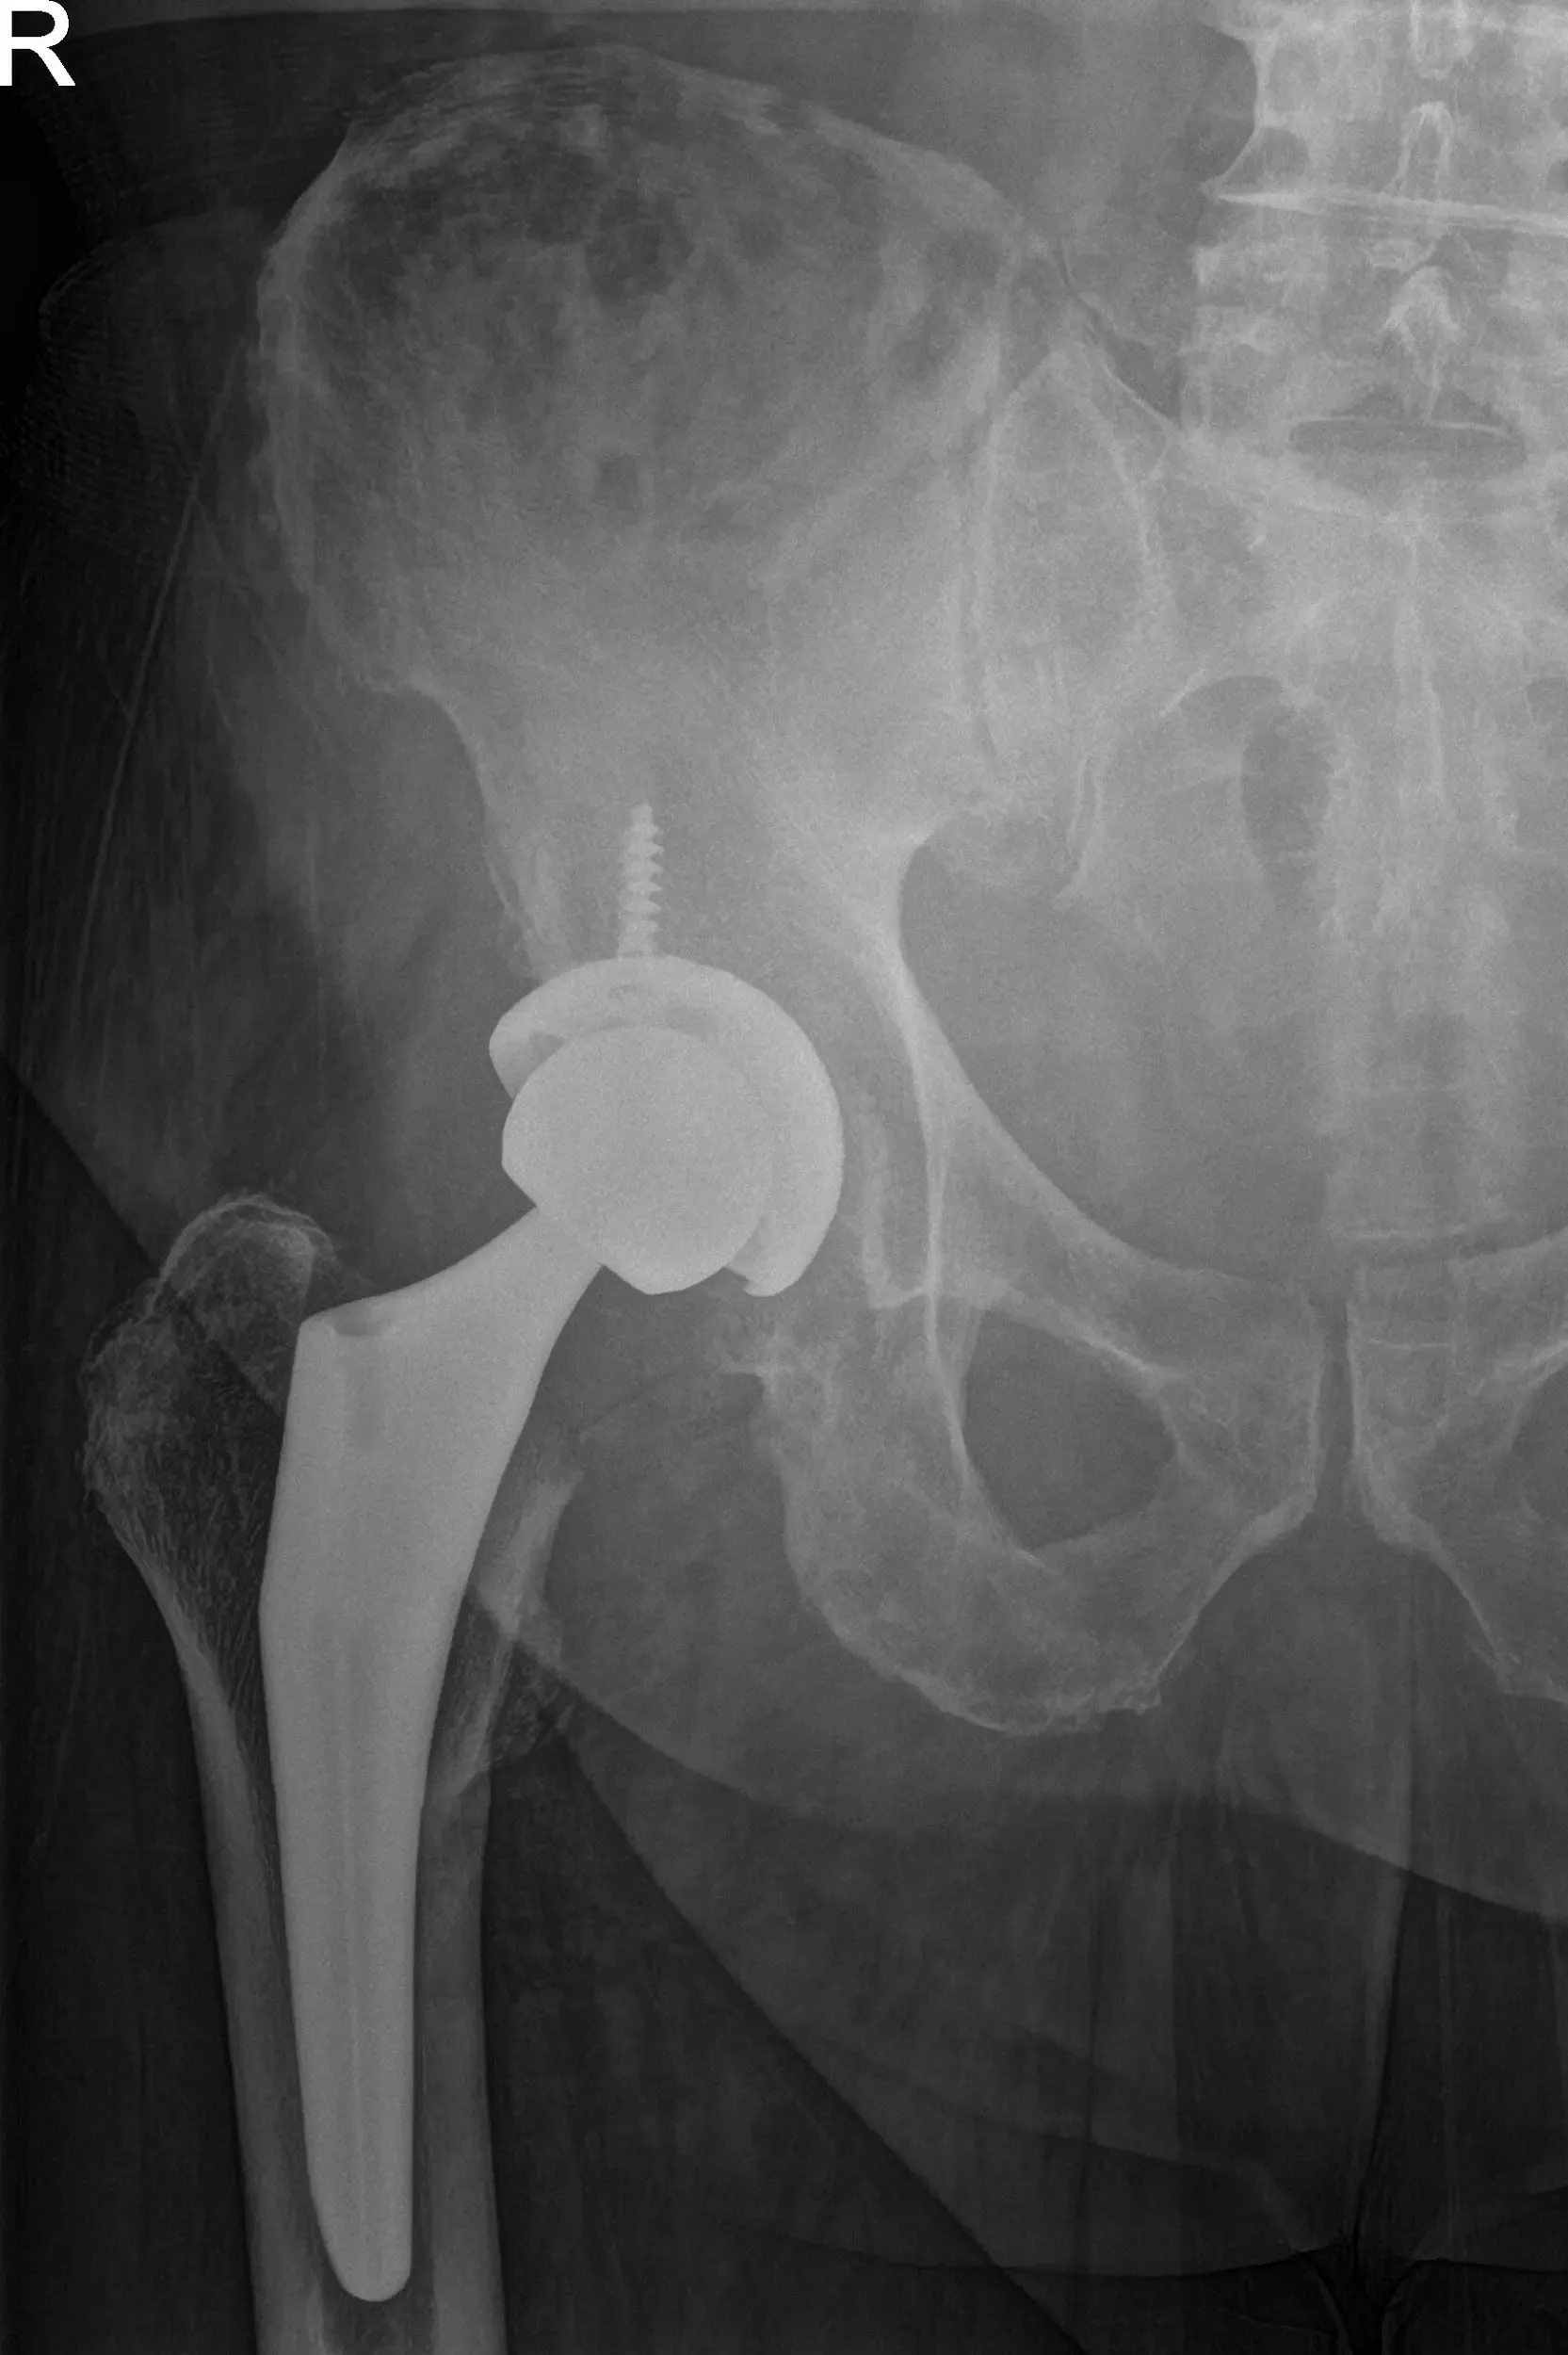

OPERATION: Right total hip arthroplasty.

IMPLANTS USED: 52 mm cup with 6.5 mm screw, 25 mm in length with a 0-degree polyethylene with a 127-degree neck stem with a ceramic femoral head 36 mm minus 2.5.

Neck resection was made at the correct level. Attention was then turned towards the acetabulum. The remainder of the labrum was then debrided. The acetabulum was then sequentially reamed. The final shell was then placed into position in the correct abduction and anteversion. A screw was used for additional fixation. A poly was then placed over the shell and attention was then turned towards the femur.

The femur was then sequentially broached. The final broach was left into position. The trunnion and the head were then placed over the stem. Lesser trochanter distance was measured and was found to be correct. The hip was then relocated. Trialed for a physiological range of motion.

There was no impingement. The stability was good. The hip was then dislocated. The trial components were then removed. The final components were then placed into position. The hip was then reduced. Thorough irrigation was given. Posterior soft tissue structures were then tagged to the greater trochanter through transosseous tunnels. The fascia was closed with Vicryl and Ethibond.